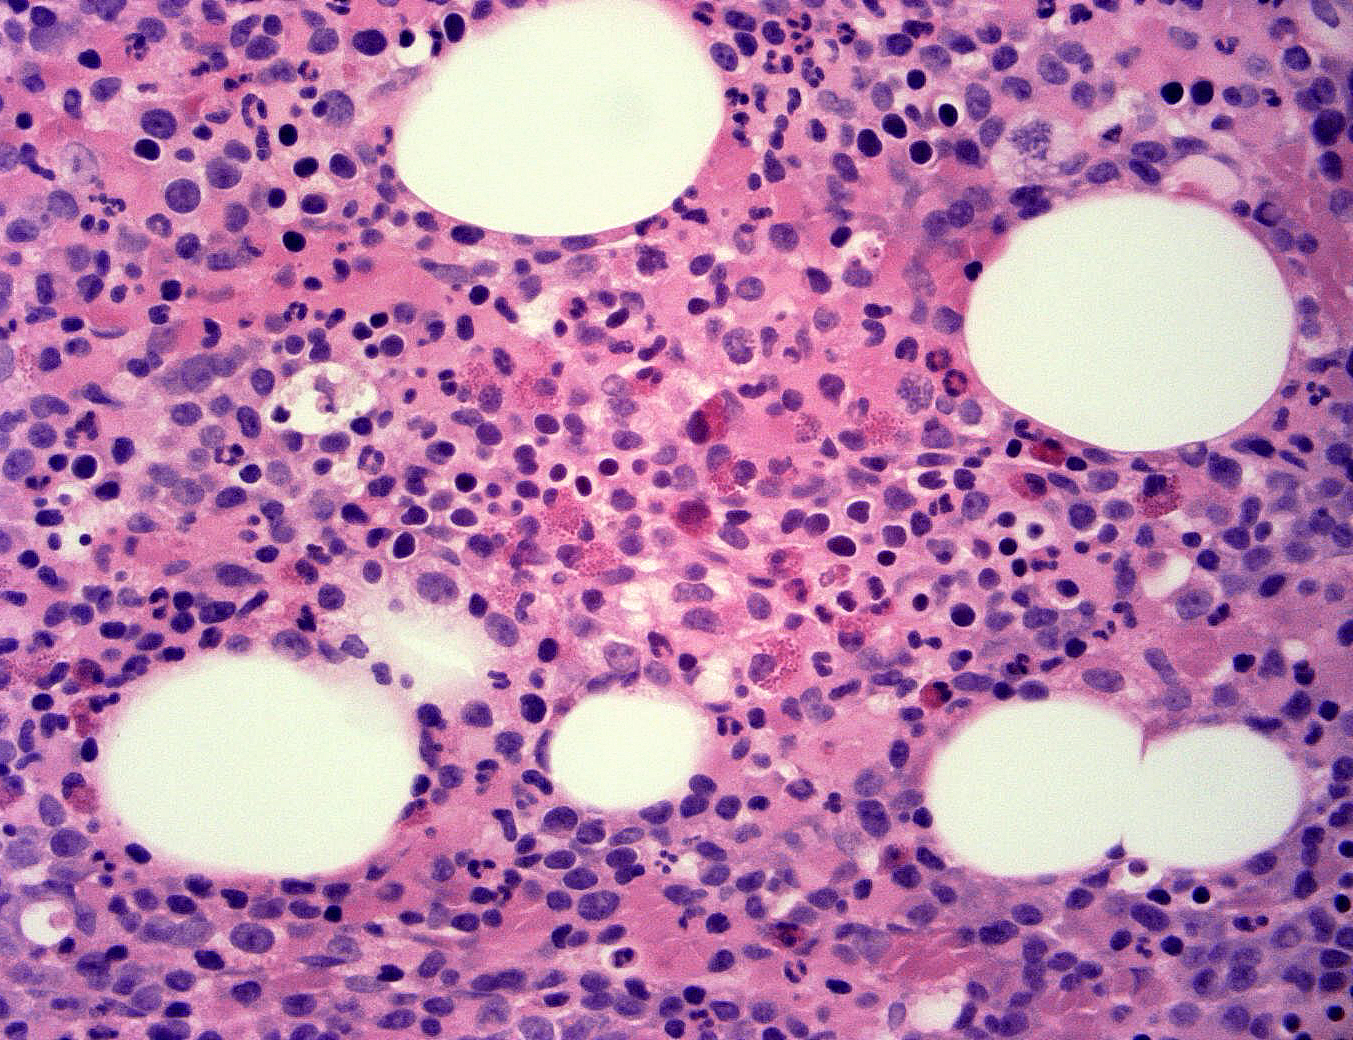

Hematopathology

Dr. Dennis Hwang is a board-certified hematopathologist and completed his hematopathology fellowship at UCSF. Contra Costa Pathology Associates offer specialized expertise in the diagnosis of various hematologic disorders including:

• Leukemias

• Lymphomas

• Myeloproliferative neoplasms

• Myelodysplastic syndromes

• Cytopenias